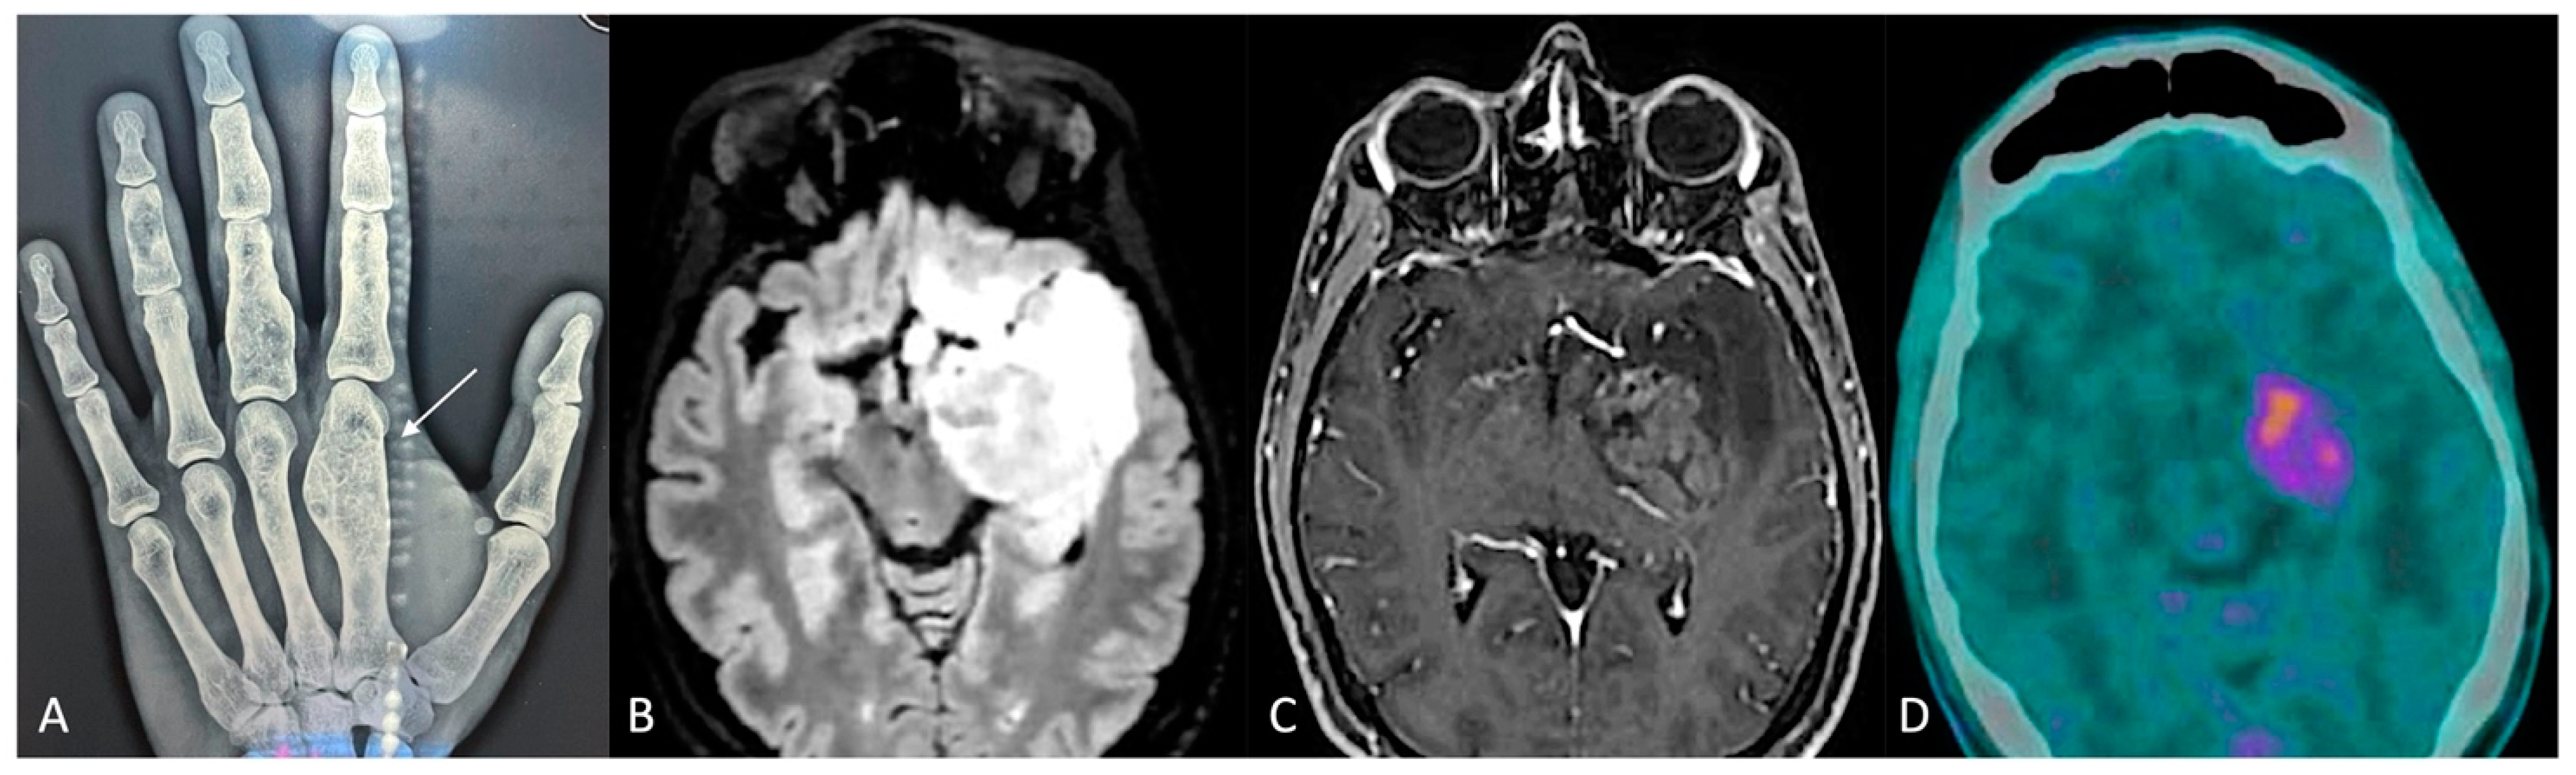

| Present case | 38/M | Enchondromatosis OD | IDH1 R132H | Surgery | No | No | Stable | |

| Astrocytoma grade 4 | IDH1 R132H | Surgery | From low-grade at MRI | RT + CHT | Stable at 3 months | |||

| Acute Myeloid Leukemia | IDH1 R132H | Induction chemotherapy follower by ATS | Relapsed AML with IDH1 R132 H mutation persistence | Allogeneic hemopoietic stem cell transplantation | Complete remission with IDH1 R132 H mutation lost | |||